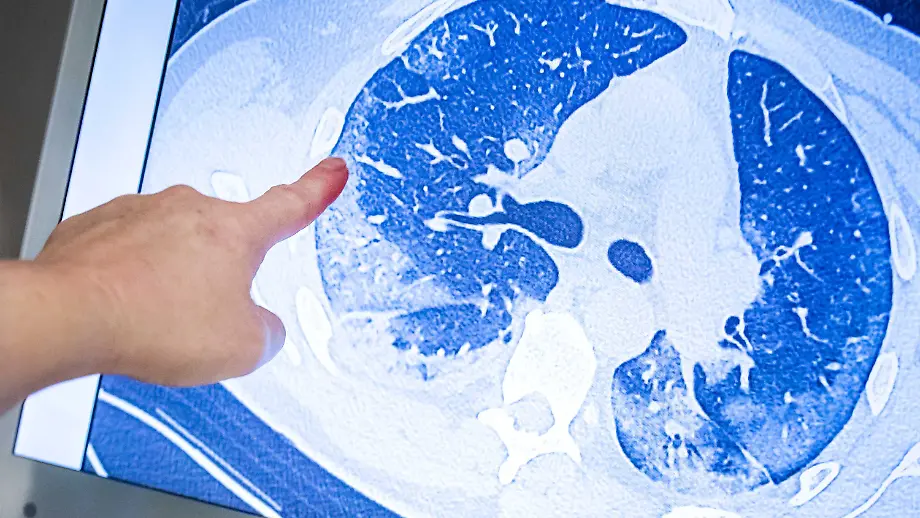

Heimtückisches VirusViele Covid-19-Patienten leiden unter Spätfolgen

23.01.2021, 16:07 UhrGut 1,7 Millionen Menschen in Deutschland durchleben bislang eine Corona-Infektion. Doch nicht alle sind dauerhaft genesen. Laut einer Studie aus China leiden fast 80 Prozent der Patienten mit einem schweren Verlauf an Spätfolgen. Aber auch leichte Verläufe können Spuren hinterlassen.